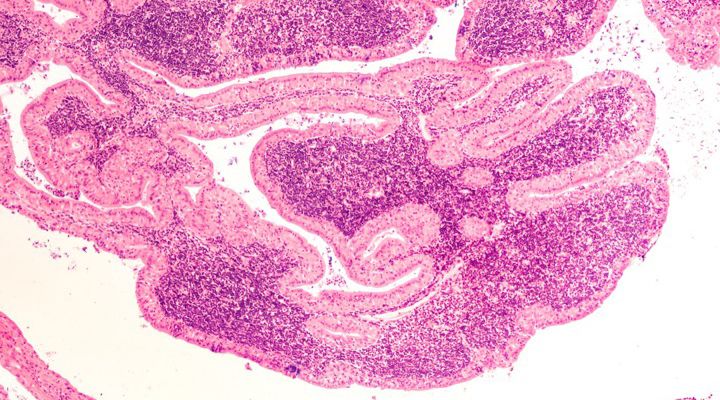

Salivary Tumors

Most salivary tumors are benign and they are not cancers. They do not usually invade adjacent tissues or metastasize, but they can continue to grow and become deforming. Benign salivary tumors are usually best removed through surgery, although there is no urgency to do so, according to Stanford Health Care.

Salivary Gland

The salivary glands produce saliva to moisten the mouth and to help protect teeth from decay and to digest food. The most common problems in the salivary gland occur when the ducts become blocked and saliva cannot drain, as was the case for Valerie and Edith.